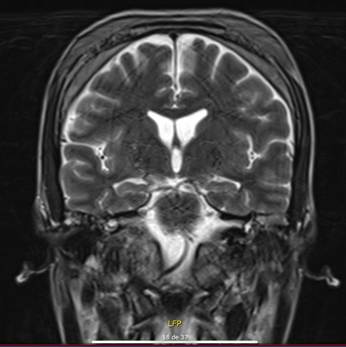

Frente a la progresión clínica con compromiso óseo inusual, hipercalcemia maligna y recaída post-quimioterapia, se decidió iniciar tratamiento de rescate con ciclofosfamida y un inhibidor de BTK (ibrutinib 420 mg/día). A las 6 semanas de iniciado el tratamiento, se evidenció remisión de la hiperplasia gingival, resolución de las protrusiones óseas frontales y maxilares, y normalización del calcio sérico (Figuras 4A y 4B). El paciente evolucionó favorablemente, sin eventos adversos relevantes asociados a la terapia dirigida.

Figura 4A. Fotografía clínica intraoral que evidencia la mejoría de la hiperplasia gingival tras tratamiento con ibrutinib. Se observa resolución de la infiltración gingival previamente documentada, con normalización del contorno gingival y disminución del volumen de los tejidos blandos. 4B. Imagen de control post-tratamiento, donde se observa reducción en el grado de infiltración ósea de la calota craneana en comparación con estudios previos.